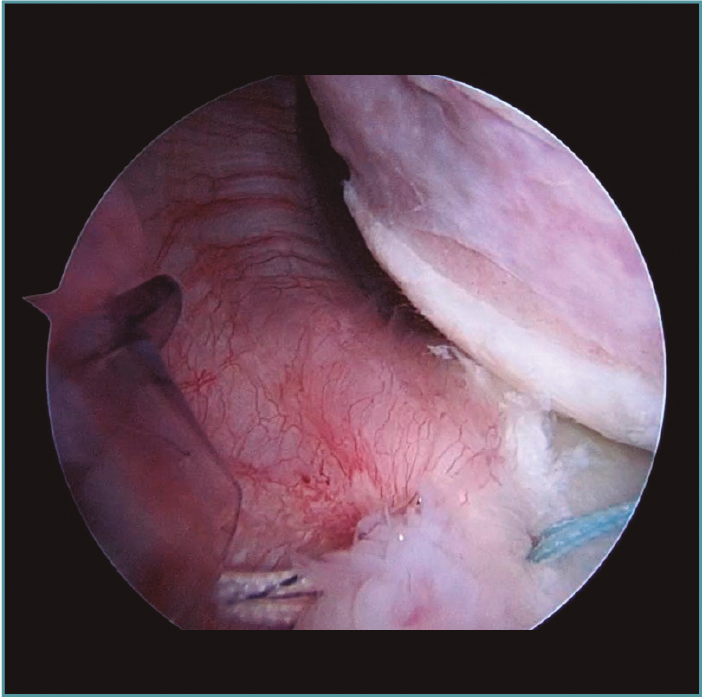

A excepción de los pacientes con significativos déficit óseos o recidivas con una mala calidad de tejido capsular, realizamos una técnica de reparación artroscópica. Operamos siempre con el paciente en decúbito lateral, con anestesia regional y general. Utilizamos siempre 4 portales instrumentales y un portal superior visual de exploración. Comenzamos nuestras cirugías con un portal de visión posterosuperior y un portal anterior de trabajo. Dependiendo de los hallazgos, realizamos las plicaturas capsulares que sean necesarias. En repetidas oportunidades encontramos hiatos intracapsulares, como por ejemplo entre el ligamento glenohumeral medio y superior, o laxitudes capsulares centrales, tratando los mismos con suturas de superior a inferior para generar una plicatura similar al capsular shift, incluso aumentando el espesor capsular (Figura 3). Luego de reparar estos defectos capsulares, seguimos nuestras plicaturas desde posterior, a través de un portal posteroinferior accesorio, colocando un anclaje con doble sutura, realizando la reparación y/o plicatura del haz posterior del ligamento glenohumeral inferior y achicando el receso inferior agresivamente siempre con anclajes de doble sutura (Figuras 4 y 5). Luego pasamos a un portal superior de visualización, dedicamos el tiempo necesario a liberar todo el labrum anteroinferior, despegando la cápsula anterior y el labrum del subescapular para movilizar e incluso acortar la cápsula, en ocasiones resecando parte de la misma para mejorar la plicatura; siempre utilizamos una sutura de tracción anterosuperior por fuera de la cánula para traccionar el tejido. Para poder llegar lo más cercano a hora 6, el primer anclaje anterior lo colocamos por un nuevo portal percutáneo transubescapular, utilizando arpones doble sutura, usando el primer par de suturas para llevar la cápsula y el labrum hacia la glena realizando sobre esta una sutura doble de tipo colchonero para mejorar la aposición capsular (Figura 6). Luego colocamos en la mayoría de los casos 2 anclajes más para terminar la reparación, en general 4 arpones. De haber un intervalo de rotadores amplio, no vacilamos en cerrarlo con suturas (Vídeo anexo).

Figura 4. Visión desde portal posterior del hombro izquierdo. Paciente con inestabilidad de hombro hiperlaxo. Se identifica un gran receso capsular posteroinferior.

Figura 5. Mismo paciente que la Figura 4. Se visualiza la gran plicatura capsulolabral posteroinferior con un ancla de doble sutura.